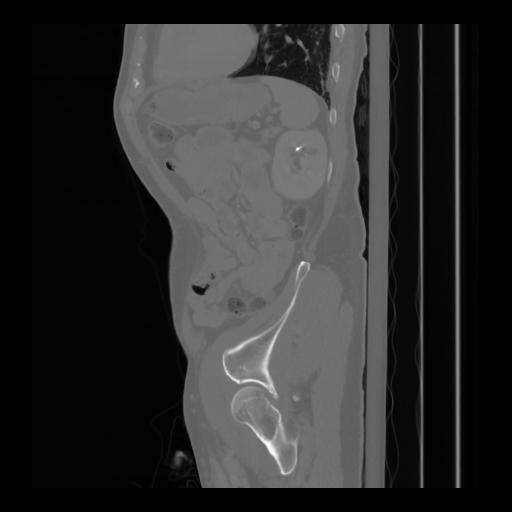

36 CUERPO,CE,Sagittal,3.000,CUERPO,Sagittal,